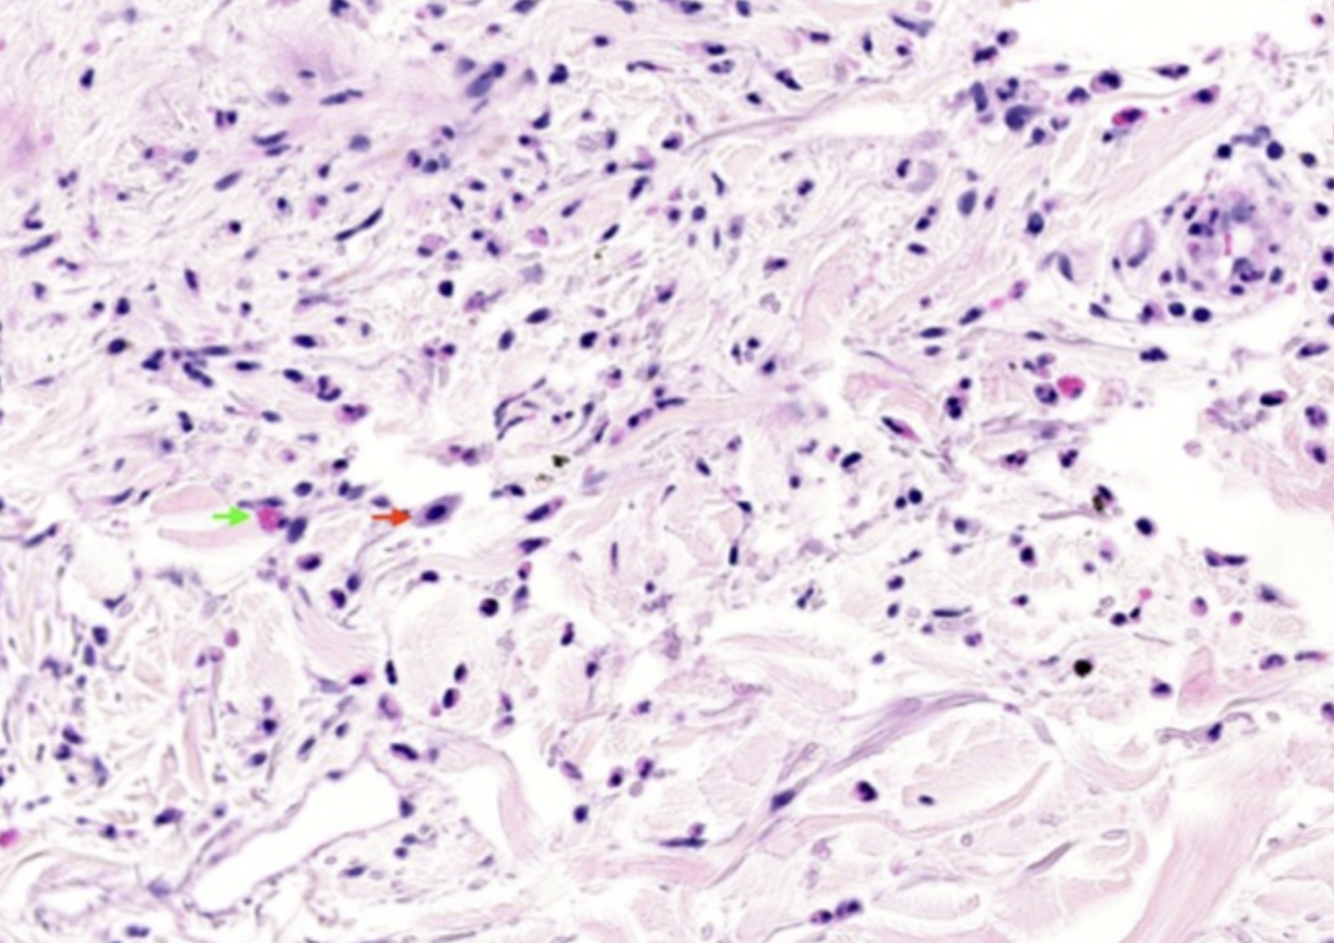

Histologie vasculite urticarienne

**Leucocytoclasie, extravasation GR, dépôts de fibrine, infiltrats neutrophiliques, oedème endothélial, oedème du derme*

Oedème du derme superficiel

Infiltrat périvasculaire léger, parfois interstitiel

mixte : lymphocytes, éosinophiles, basophiles, neutrophiles

Dommage aux vaisseaux dermiques

oedème endothélial et occlusion luminale

Leucocytoclasie

carryorhexie des neutrophiles avec poussière nucléaire

Dépôts fibrinoïdes dans les parois vasculaires

Extravasation GR

Infiltrat inflammatoire des parois vasculaires et périvasculaire

neutrophiles, éosinophiles, lymphocytes

prédominance lymphocytaire avec lésions matures

Vasculite leucocytoclasique avec nécrose des parois vasculaires avec ou sans dépôts fibrinoïdes Infiltrat avec neutrophiles ou éosinophiles GR extravasés **IFD** Dépôts Ig, C3 ou fibrinogène périvasculaire (70%) Immunoréactants granulaires membrane basale (80%) suggère LED si avec hypocomplémentémie